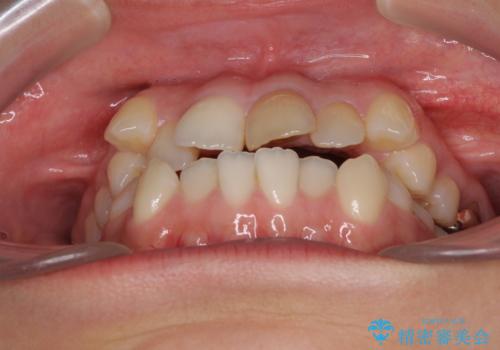

- 上の八重歯を気にして来院された患者様です。

受け口傾向にあるため、上顎前歯の叢生解消とともに下顎前歯を後方へ移動させることを目的とし、上下左右の第一小臼歯4歯を抜歯することとしました。

受け口傾向の方の下顎抜歯矯正では、下顎前歯の歯肉が退縮することがあります。前歯を移動させるときには、歯肉退縮が起こらないように工夫する必要があります。